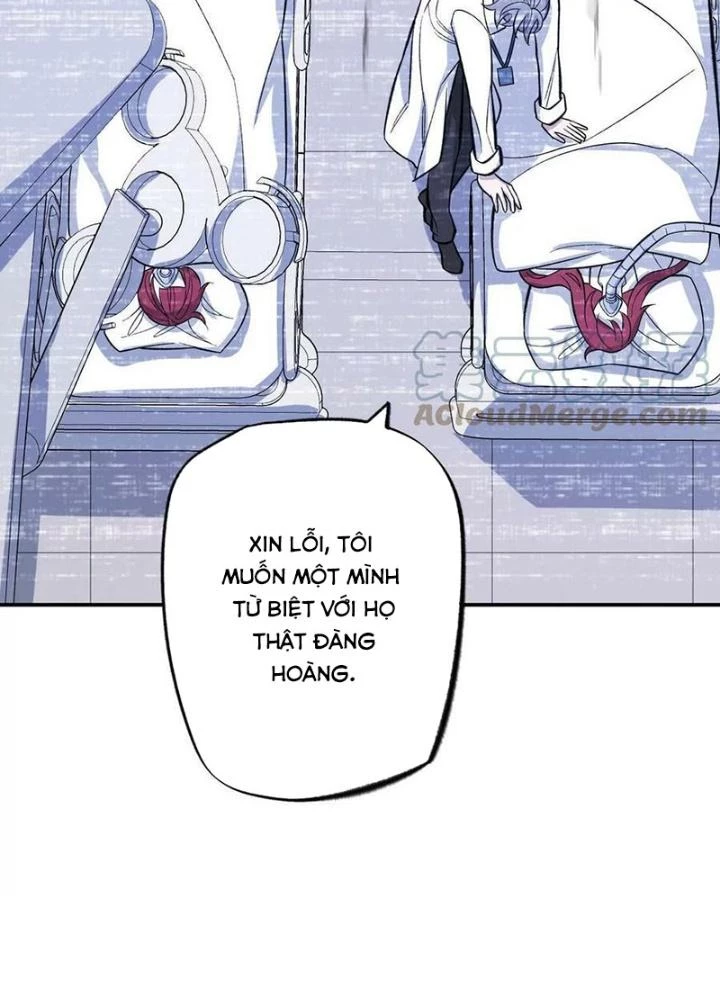

Thời Kỳ Tận Thế - Chapter 133